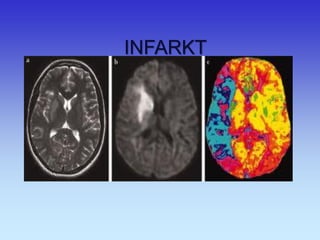

INFARKT